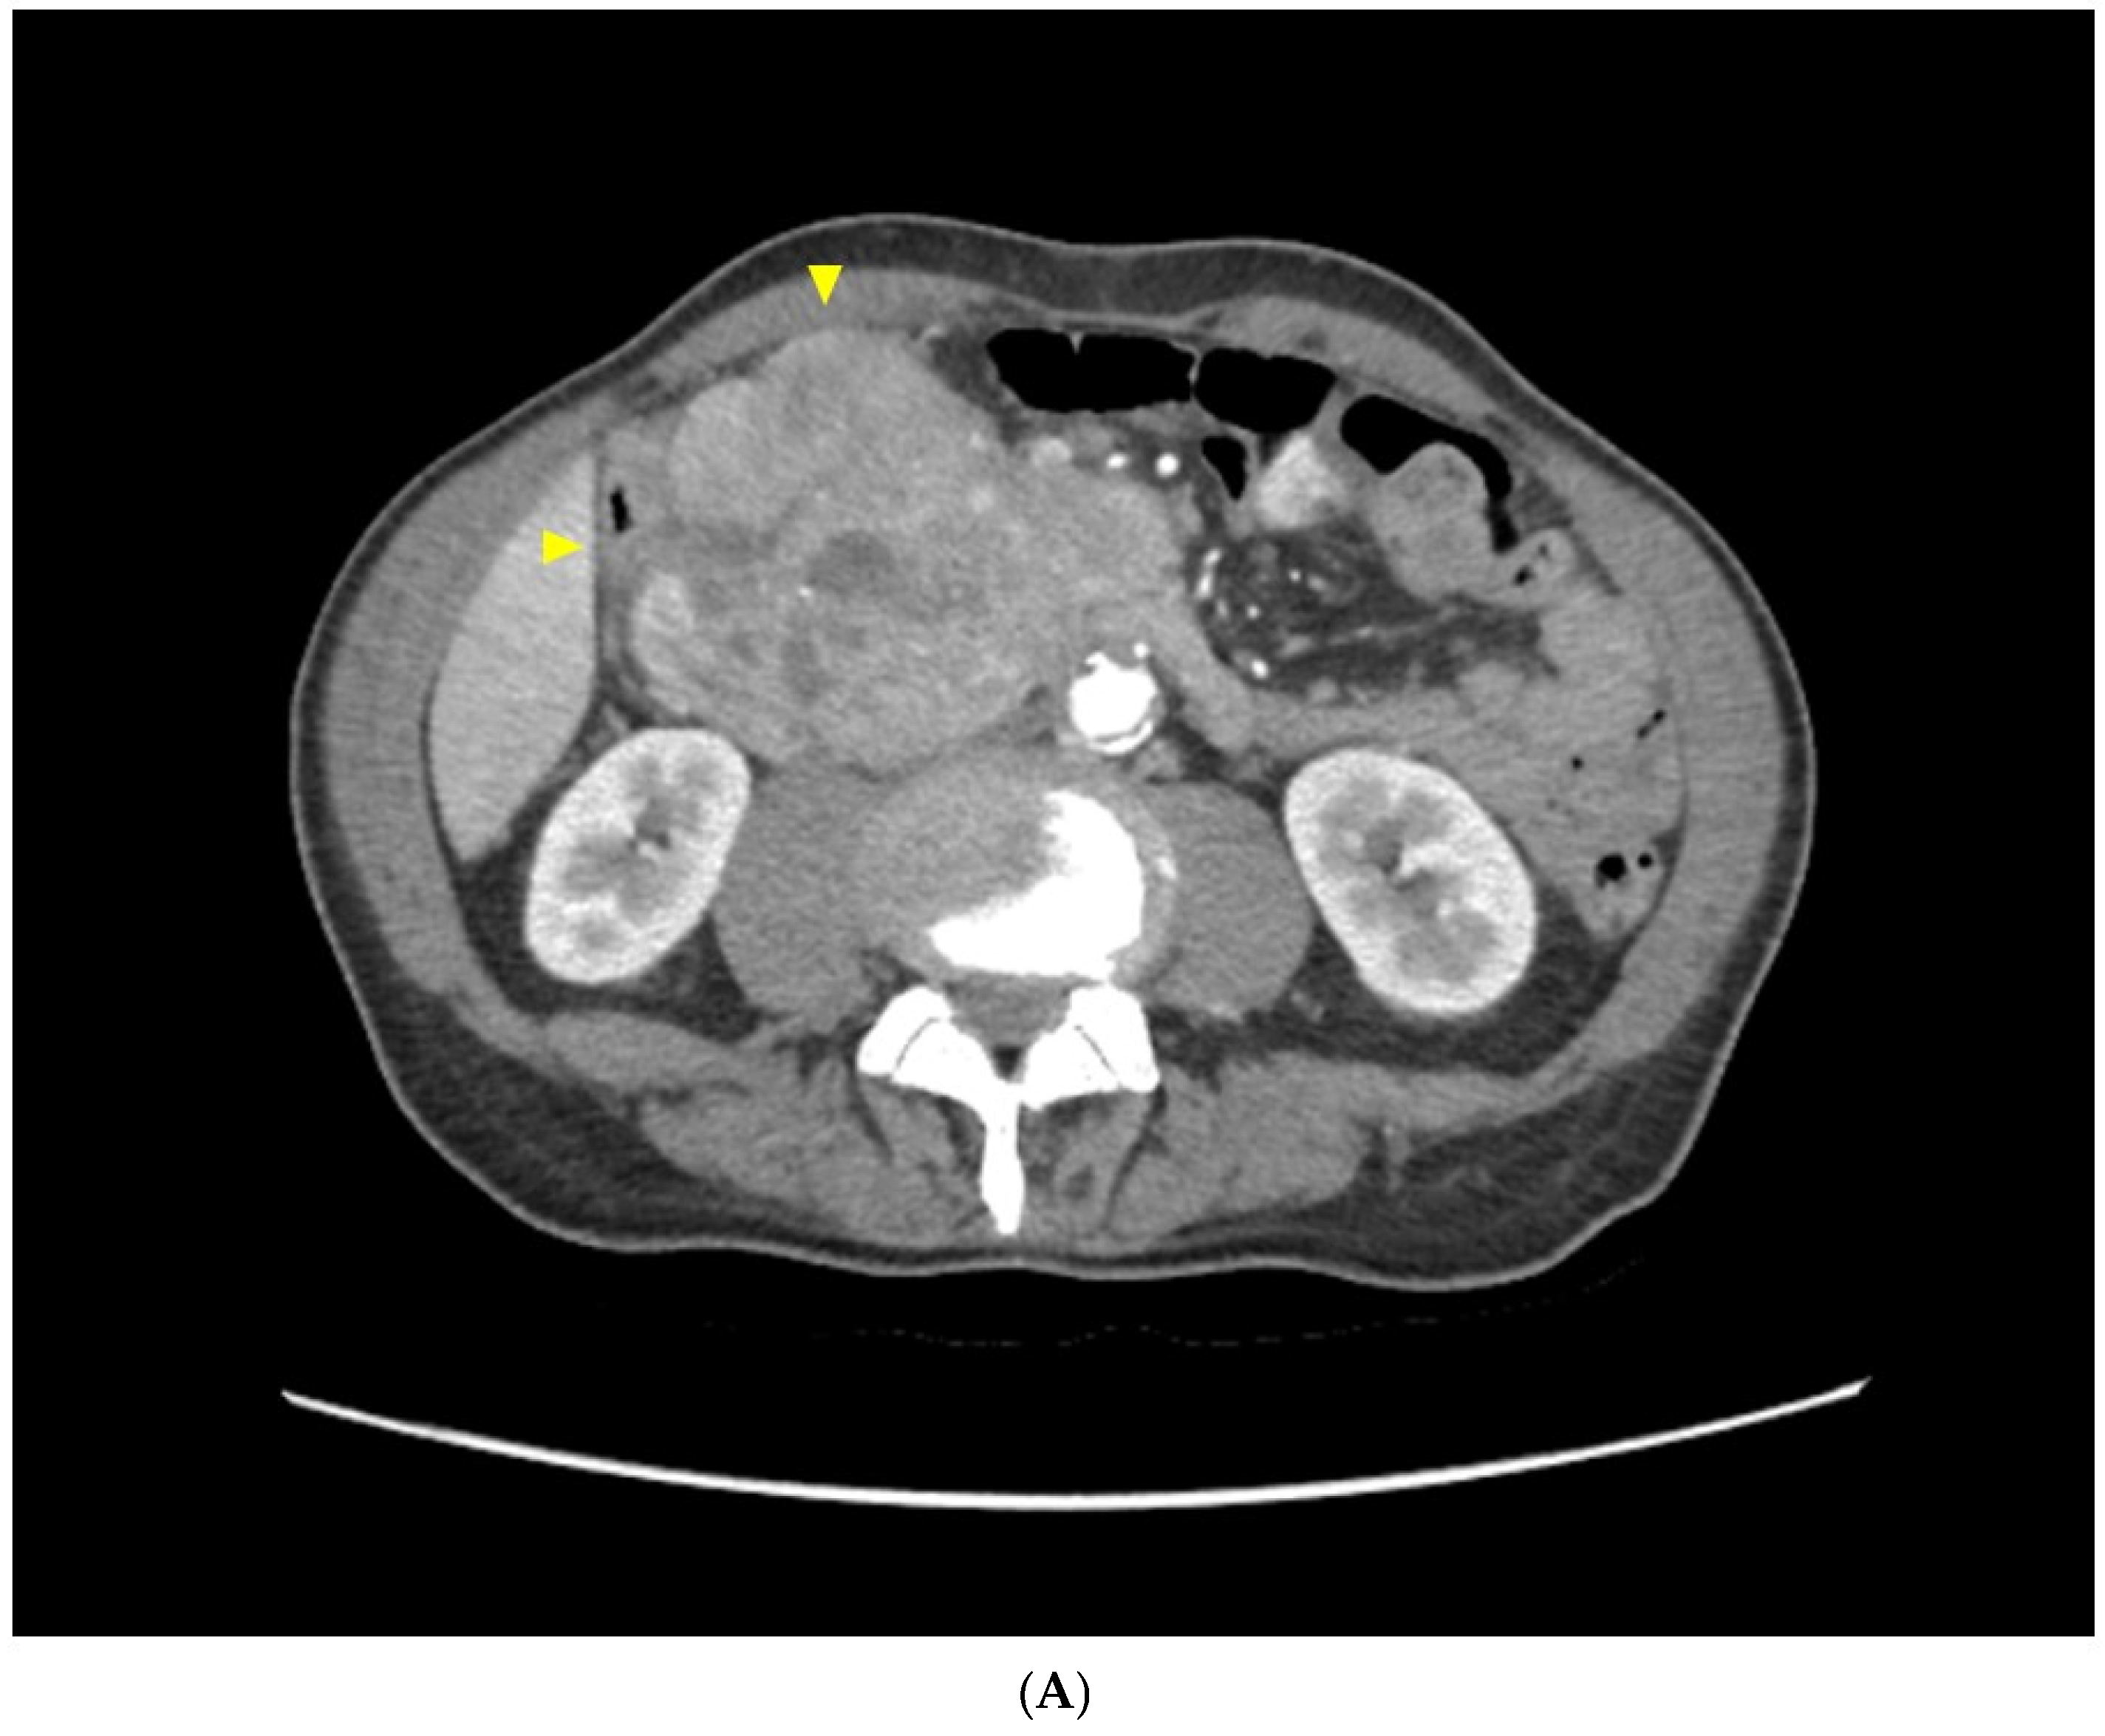

2.1. Case Report 1